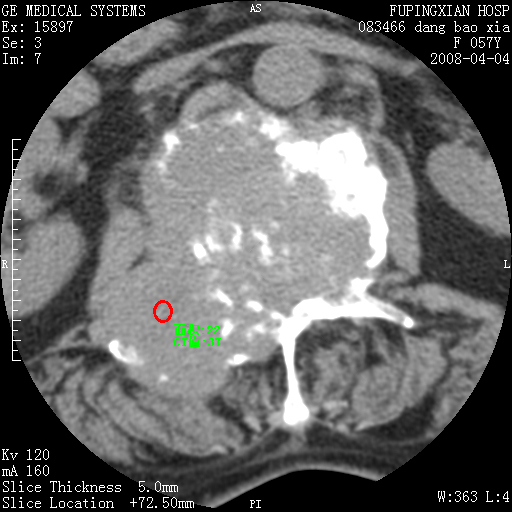

标题: CT12677:女性,57岁,疼痛数月。 [打印本页]

标题: CT12677:女性,57岁,疼痛数月。

椎体及附件骨质破坏同时伴软组织肿块,首先考虑恶性肿瘤。

椎体及附件骨质破坏,伴软组织肿块,首先考虑恶性骨肿瘤,建议提供正侧位片。

骨组织起源,膨胀,软组织肿块=恶性改变:首选骨巨,其次转移瘤,再次脊索瘤

椎体及附件溶骨性破坏,周围巨大软组织肿块,首先考虑转移瘤。